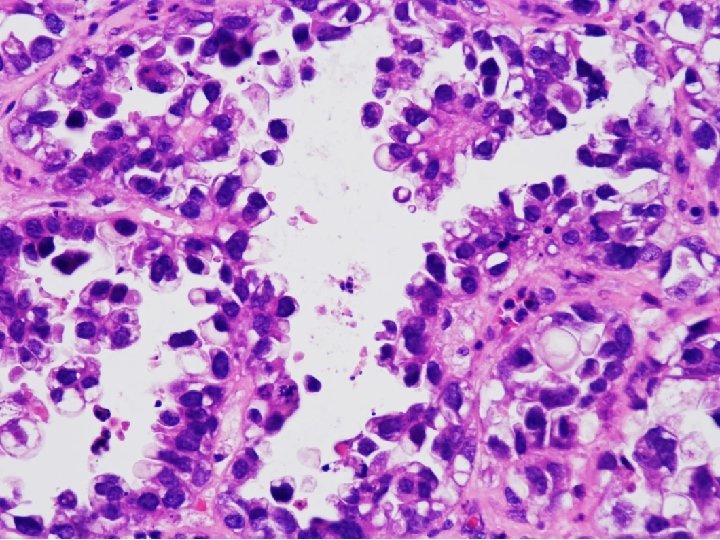

Tissue from uterine cervix, biopsy; Poorly differentiated adenocarcinoma with 1) sheets and papillary features 2) tubulocystic pattern 3) frequent clear cell feature c/w CLEAR CELL CARCINOMA

• Clear cell carcinomas present marked cellular and nuclear pleomorphism; they often have bizarre nuclei and abundant, pale cytoplasm Color Atlas of DDx in Exfoliative and Aspiration Cytopathology, Kini

CYTOPATHOLOGIC FEATURES OF CLEAR CELL CARCINOMA • Arrangement – Cells are isolated, in loosely cohesive groups and in syncytial tissue fragments; hobnail pattern may be present • Cells – Medium to large with poorly defined cell borders; moderate to high N/C ratios; round, polygonal to hobnail type • Nuclei – Large, round, often eccentric, very pleomorphic; coarsely granular to smudgy chromatin; nucleoli are inconsistent; multinucleation • Cytoplasm – Variable, scant to abundant, clear to pale, weakly staining either eosinophilic or cyanophilic • Background – Clean, bloody or inflammatory; naked nuclei Color Atlas of DDx in Exfoliative and Aspiration Cytopathology, Kini